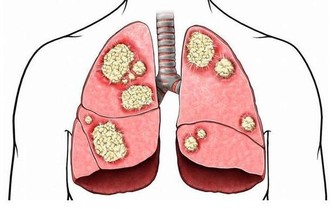

肝硬化:戒菸忌酒勤運動

肝臟是人體最大的代謝器官,我們吃進去的食物都需要肝臟進行合成、分解。在我國,每12個人中就有1人患肝病。

1、忌酒:酒精主要在肝臟被代謝,長期酗酒會傷害肝臟,脂肪肝最早出現,接下來會發展成肝纖維化、酒精性肝病,甚至轉變為肝硬化、肝癌。